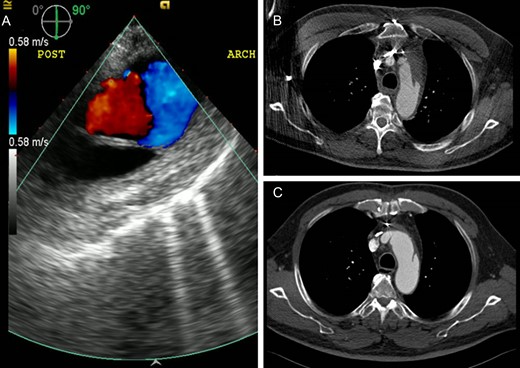

The post-cardiopulmonary bypass transesophageal echocardiogram confirmed the absence of flow in the false lumen (Fig. 2A). The patient had an uneventful recovery. He was discharged home on postoperative Day 6. Follow-up CTA demonstrated evolving changes in the aortic arch with complete thrombosis of the false lumen upon discharge and an interval resolution of the false lumen at 1 month (Fig. 2B and C). He remained well at 1 year postoperatively with stable appearance of the aorta on CTA.

Echocardiography and computed tomography demonstrate the changes of the residual false lumen in the distal aorta. (A) Absence of blood flow in the false lumen on transesophageal echocardiography after the repair. Follow-up computed tomography scans showing interval thrombosis of the false lumen on postoperative Day 5 (B) and complete resolution of the false lumen at 1 month (C).